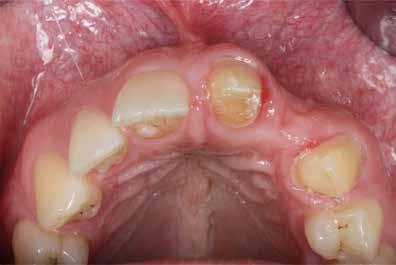

Az alább bemutatott eset kezelési tervében egy szóló implantátum behelyezését határozták meg az esztétikailag kihívást jelentő front maxilla bal felső kismetszőfogának a helyére.

1. ábra: Lokalizált horizontális gerincdefektus. A kezelési terv szerint szóló implantátumot helyeznek a kismetszőfog helyére.